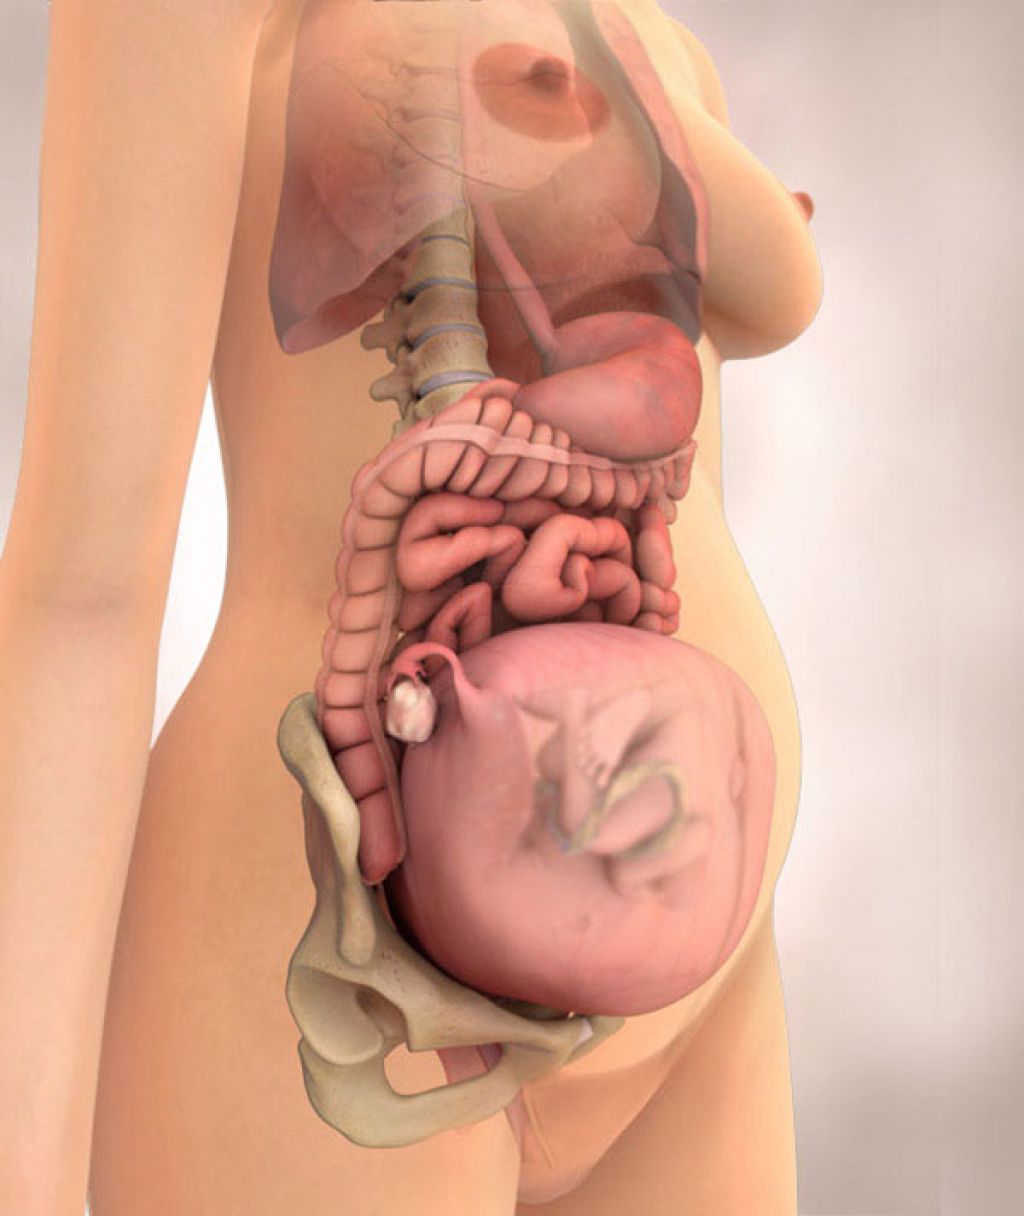

Фотография Плода В Животе

Фотография Плода В Животе 113 фотографий